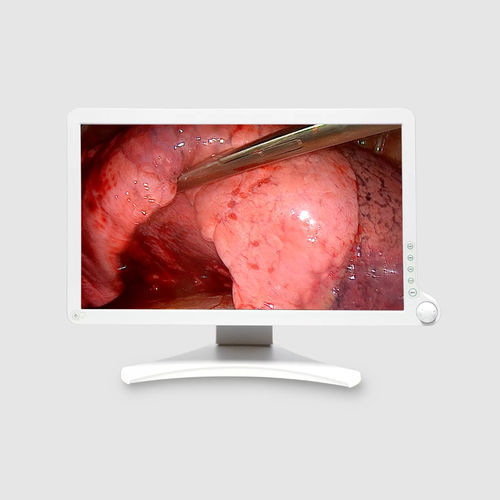

Medizinischer Full-HD-21,5-Zoll-Touchscreen

Der AMM 215WTTP ist ein 21,5-Zoll-Touchscreen, der für medizinische Fachkräfte entwickelt wurde, die eine präzise und zuverlässige Interaktion mit der Touch-Benutzeroberfläche benötigen.

Ergonomische Interaktion

Der AMM 215WTTP ist für mehr Ergonomie entwickelt worden. Der 21,5-Zoll-Bildschirm ist einfach zu bedienen und verfügt über die perfekte Größe und das perfekte Format für eine Vielzahl von Anwendungen, einschließlich digitalen OPs und Medizinwagen. Dank seiner Full-HD-Auflösung hat das klinische Personal Zugang zu umfassenden Detailinformationen.

Das Display verfügt über die Technologie Projected Capacitive Touch mit Multi- und Single-Touch-Funktionalität. Es ermöglicht den klinischen Personal auch beim Tragen von Handschuhen problemlos mit der Benutzeroberfläche auf dem Monitor zu interagieren.

ür medizinische Umgebungen entwickelt

Der AMM 215WTTP ist medizinisch zertifiziert und für den Einsatz in einer anspruchsvollen, erfolgskritischen Umgebung wie dem OP-Raum geeignet. Das rahmenlose Design ermöglicht einfache Reinigung und Desinfektion, eine wesentliche Voraussetzung für alle chirurgischen und klinischen Umgebungen.